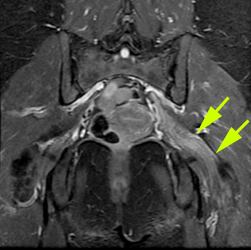

Neuroradiology focuses on imaging and therapies to diagnose and to treat disorders of the adult and pediatric brain, spine, neck, and central and peripheral nervous system. The UCSF neuroradiology group is comprised of internationally recognized experts in every one of these disciplines, and in the latest state-of-the-art imaging with CT, MRI, MEG and molecular modalities such as PET. The group has expertise in the full array of neurologic disease, including brain tumors, stroke and other vascular disorders, spine disease, neurodegenerative diseases, and brain malformations. With 12 full-time neuroradiologists across our campuses, we are one of the largest divisions of neuroradiology in the United States.

Patients are referred to UCSF neuroradiology from all over the world. Each year we perform and interpret over 14,000 CTs, 22,000 MRIs, 250 myelograms, more than 1,000 diagnostic angiograms, over 650 interventional procedures, and more than 500 spinal procedures including biopsies, nerve root block, epidural injections of steroids and specialized procedures including vertebroplasty and kyphoplasty. For example, we offer special expertise and apply advanced cutting edge MRI techniques for the diagnosis and monitoring of patients with brain, skull base and ENT tumors, traumatic brain injuries, the range of pediatric brain and spine disorders as well as for patients with spine related pain. Because we perform an unusually high number of procedures each year, referred from a variety of specialists, we have gained enormous clinical and scientific expertise. That expertise leads to more precise diagnoses and better clinical judgment and skill. It also directly facilitates our ability to help patients and their doctors by sharing our skills in “seeing,” detecting, and treating abnormalities. This allows us to provide informative consultations to referring physicians and to suggest proper interventions.

Neuroradiology Advanced Techniques and Technologies

At UCSF we have the highest quality imaging equipment and use the appropriate one for the task at hand in order to achieve crisper, better, more detailed, higher resolution images for patients.